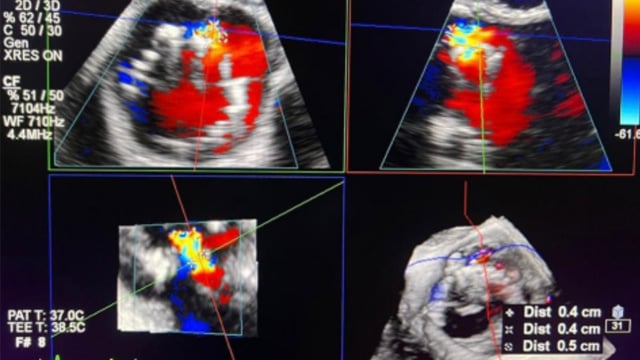

Rapid-Fire - Paravalvular leak closure

Dive into a rapid-fire session showcasing a variety of challenging paravalvular leak closure cases. Witness innovative techniques and strategies, such as utilizing aortic paravalvular defects as a neopathway for mitral paravalvular leak closure, the coronary balloon technique for multiple paravalvular leaks, and zero-contrast percutaneous closure of...